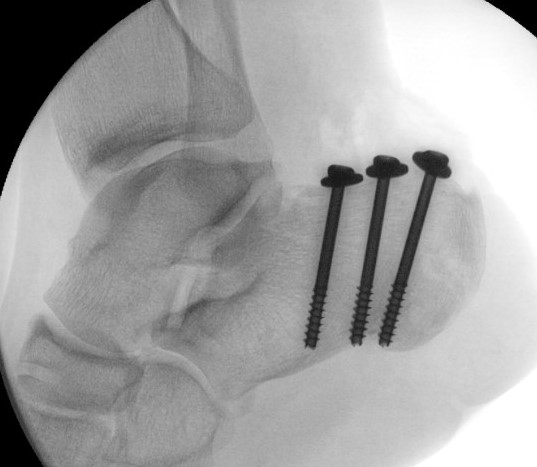

Sustentacular fractures

ORIF if displaced

Medial approach with buttress plate